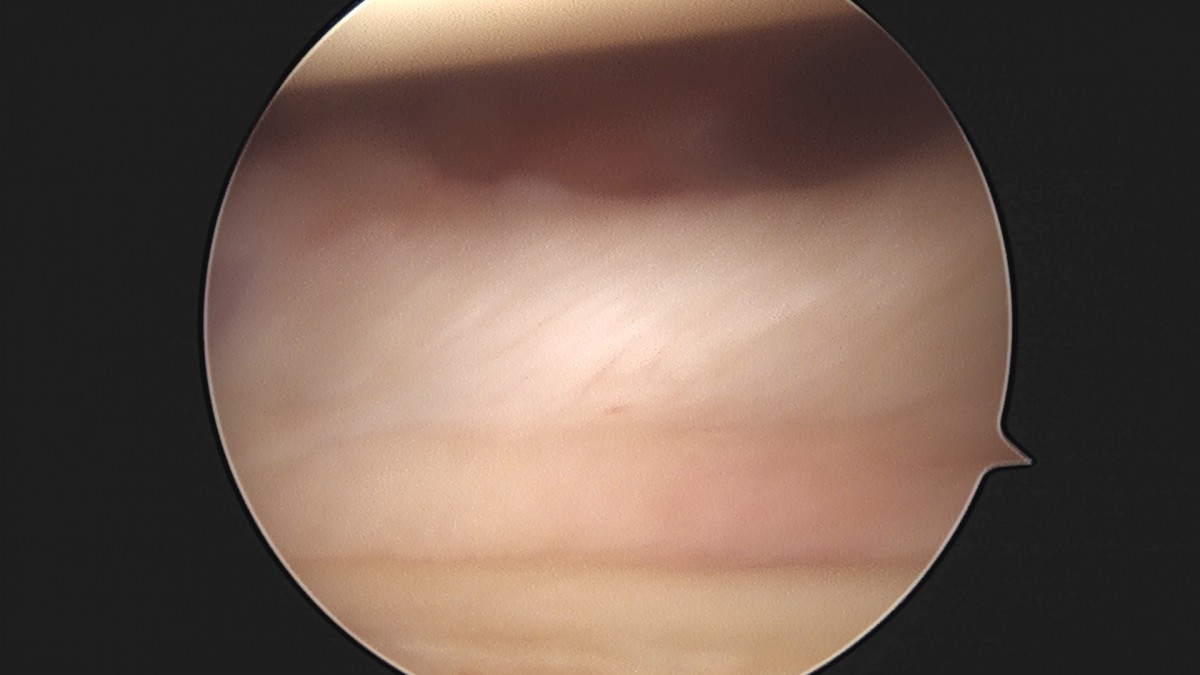

이재상원장님 어깨 석회 제거술 조광O 환자

dae765e4d9ac96aee867c9d6292d8784_1758004693_7301.jpg